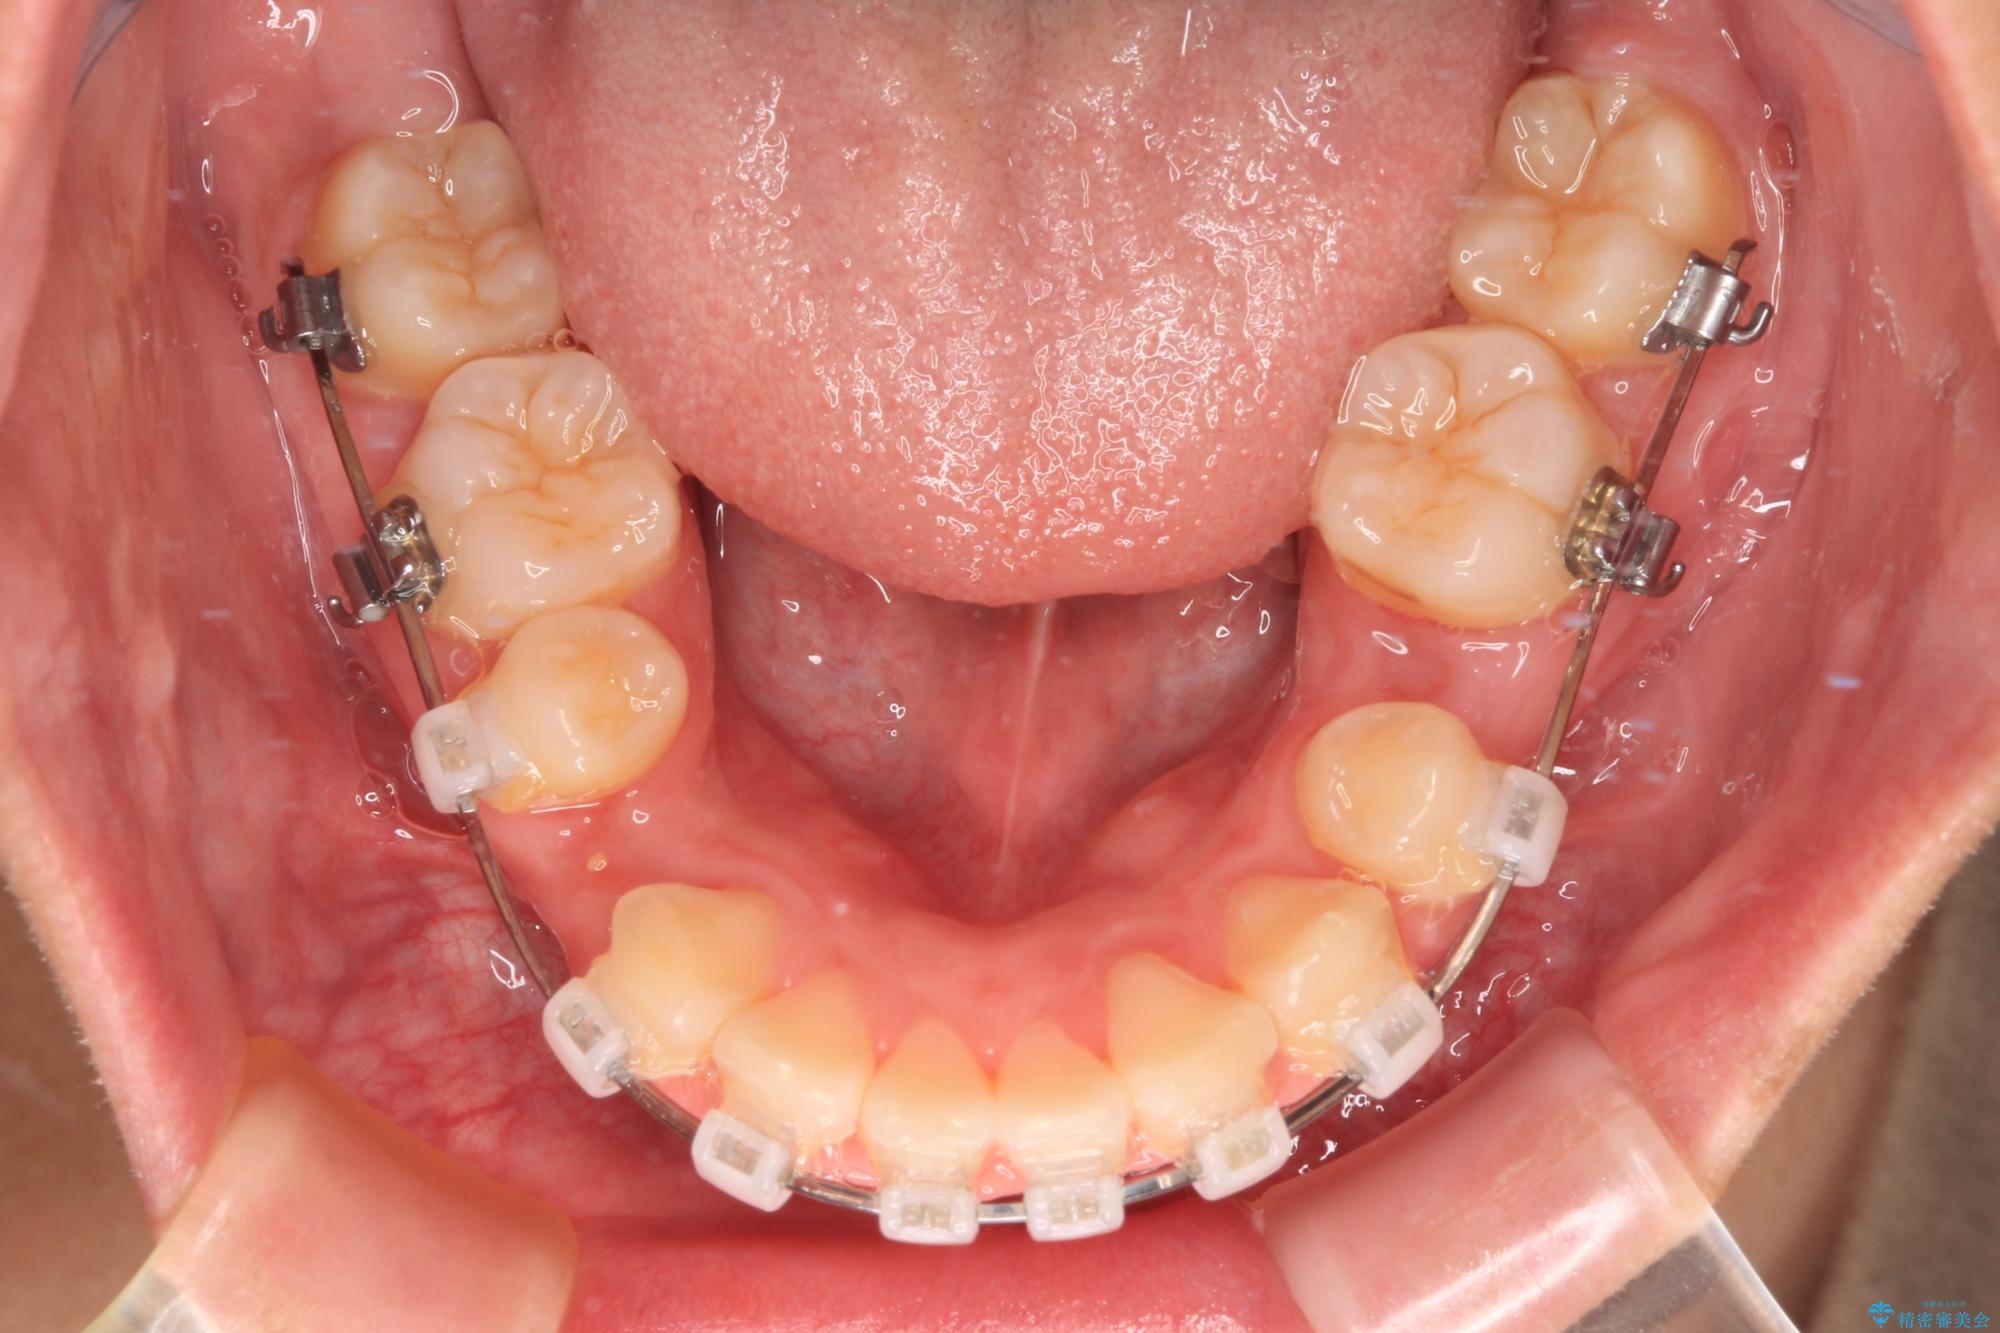

- 矯正装置

- クリアブラケット

くちばしのように前歯が突出していたため、口元を積極的に引っ込めるために、上下左右の小臼歯4本を抜歯することとしました。

また、上顎歯列が下顎に対して前方位に位置していたため、補助装置を用いて上顎歯列を後方に移動させ、より積極的に口元を下げるようにしました。

上下正中位置を改善するため、左下はイレギュラーに第二小臼歯を抜歯しました。そのため治療期間の長期化が予想されましたが、2年半ほどで期待通りの歯列に仕上げることができました。